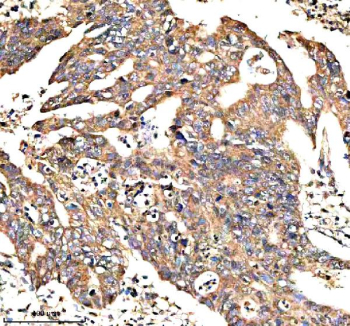

IHC analysis of NEK9 using anti-NEK9 antibody. NEK9 was detected in a paraffin-embedded section of human colon cancer tissue. Heat mediated antigen retrieval was performed in EDTA buffer (pH 8.0, epitope retrieval solution). The tissue section was blocked with 10% goat serum. The tissue section was then incubated with 2 ug/ml rabbit anti-NEK9 antibody overnight at 4oC. Peroxidase Conjugated Goat Anti-rabbit IgG was used as secondary antibody and incubated for 30 minutes at 37oC. The tissue section was developed using an HRP secondary and DAB substrate.